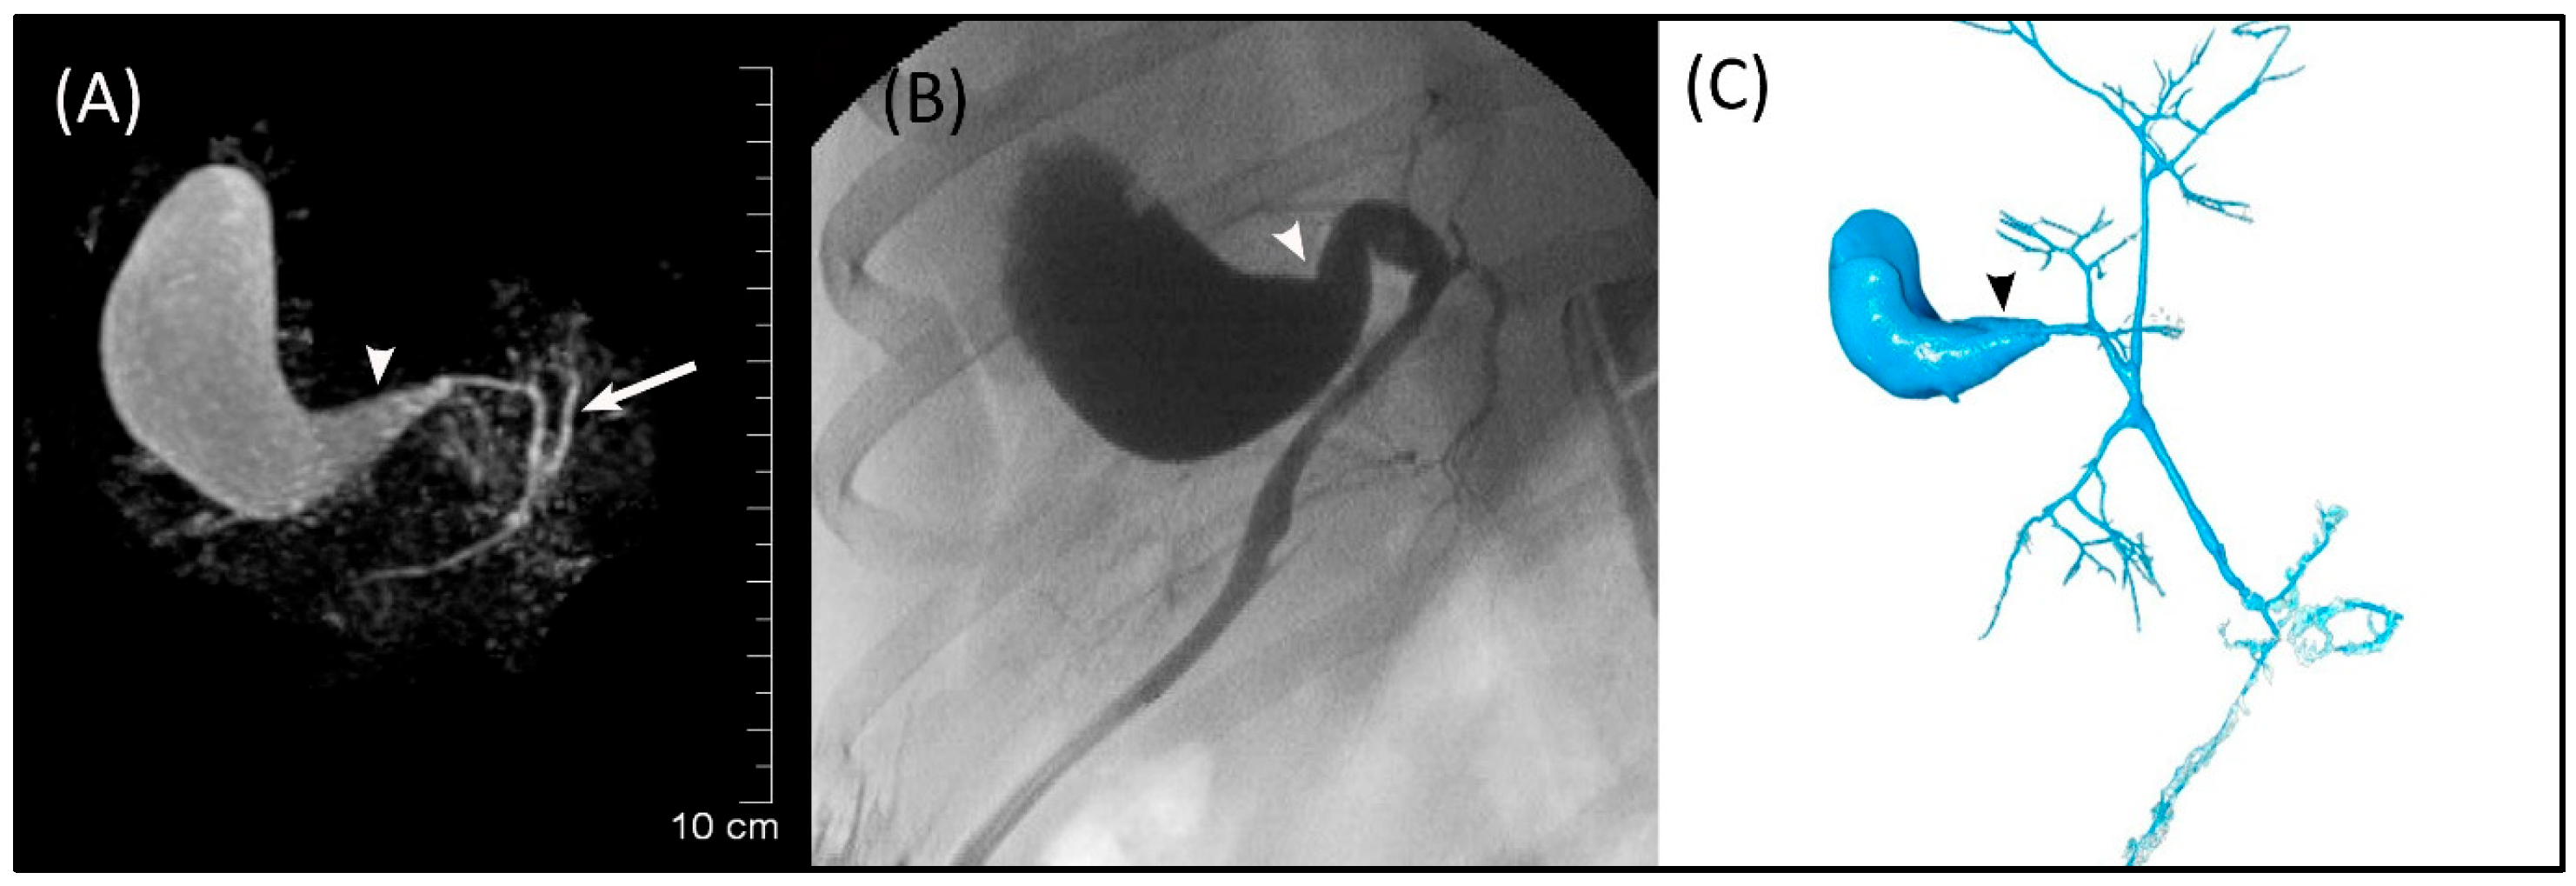

The GB (fundus, body, and neck), cystic duct, and CBD (at papilla and at extrahepatic ducts’ junction) were visible in MRCP, FRCP, and corrosion casting in all eight dogs. Visual comparisons between MRCP, FRCP and corrosion casting in Dog 6 with no evidence of disorders and Dog 8 with biliary disorders are shown in Figure 2 and Figure 3, respectively. The extrahepatic ducts and pancreatic ducts were variably visible in the MRCP and FRCP images. This did not allow for statistical analysis, only descriptive assessment.

Figure 3. Images of Dog 8 with acute extrahepatic cholestasis and focal destructive cholangitis. (A) 3D-TSE-MRCP illustrating dilated gallbladder neck (arrowhead). Normal left extrahepatic duct is visible (arrow). (B) FRCP image showing dilated gallbladder neck (arrowhead). (C) Corrosion cast demonstrating dilated gallbladder neck (arrowhead).